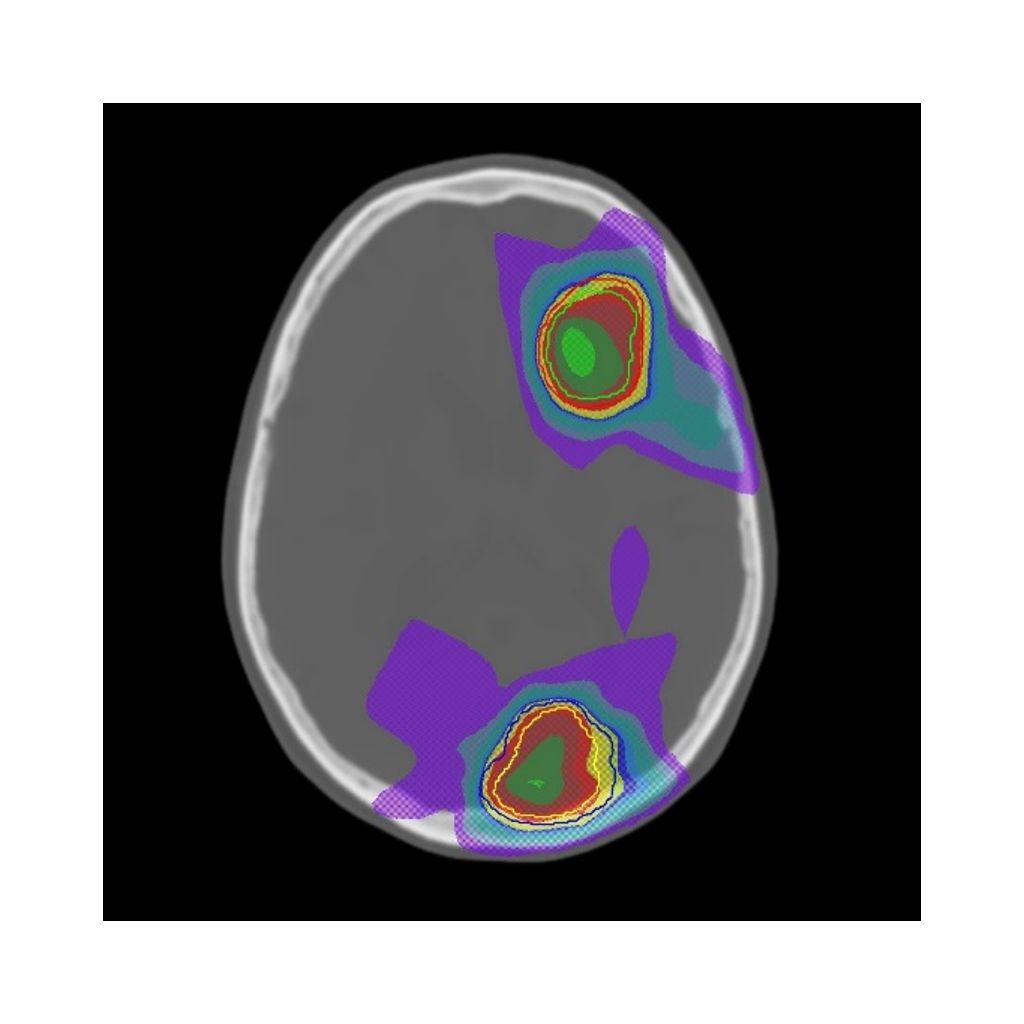

MRCAT Brain

MRCAT Brain is intended for radiotherapy planning of primary and metastatic tumors. MRCAT Brain creates Pseudo CT, while allowing the usage of contrast agent. The MRCAT Brain source scan comes with a sub millimeter resolution for contouring purposes and is the base for calculating Pseudo CT.

Onesite web image MRCAT Brain